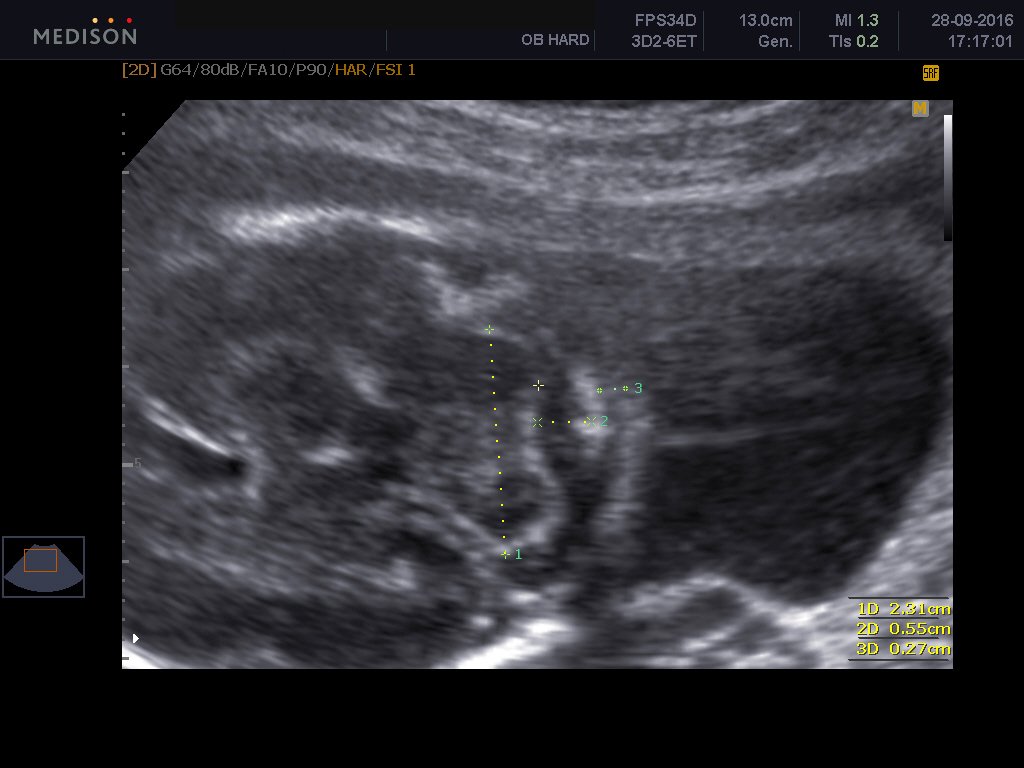

To υπερηχογράφημα β επιπέδου είναι ειδικό υπερηχογράφημα το οποίο εκτελείται από εξειδικευμένο ιατρό και με το οποίο ελέγχεται λεπτομερώς η ανατομία του εμβρύου. Γίνεται όπως όλα τα υπερηχογραφήματα δια μέσου της κοιλιακής χώρας της εγκύου και είναι απόλυτα ανώδυνο.Είναι δυνατόν το υπερηχογράφημα να απεικονίσει σοβαρές συγγενείς ανωμαλίες του εμβρύου καθώς και ελαφρές ανατομικές βλάβες. Επίσης αναγνωρίζει υπερηχογραφικά σημάδια , τα καλούμενα markers , με τα οποία υποπτευόμαστε σοβαρά χρωμοσωμιακά σύνδρομα εμβρύου, όπως το σύνδρομο Down, την trisomy 18 και trisomy 13. Γίνεται έλεγχος του πλακούντα εκτιμάται το αμνιακό υγρό καθώς και η προβολή του εμβρύου και ο τράχηλος της μήτρας και ειδικά το μήκος τραχήλου μας δίνει πληροφορίες όσον αφορούν τον πρόωρο τοκετό.

Ελέγχεται το κρανίο, ο εγκέφαλος, το πρόσωπο, η καρδιά, τα χέρια, τα πόδια, η σπονδυλική στήλη, η ουροδόχος κύστη του μωρού. Μερικές συγγενείς βλάβες που μπορεί να αναγνωρίσει το υπερηχογράφημα είναι οι εξής: Ανεγκεφαλία, ανοιχτές βλάβες νωτιαίου σωλήνα , χειλεοσχιστία -λαγόχειλος, διαφραγματοκήλη, γαστρόσχιση , εξόμφαλος, σοβαρές καρδιακές συγγενείς ανωμαλίες, αγενεσία νεφρών, πολυκυστικούς δυσπλαστικούς νεφρούς, θνησιγενείς σκελετικές δυσπλασίες.

Το υπερηχογράφημα είναι κοιλιακή εξέταση. Υπάρχει περίπτωση να χρειαστεί επιπρόσθετα και διακολπική εξέταση του τραχήλου της μήτρας.